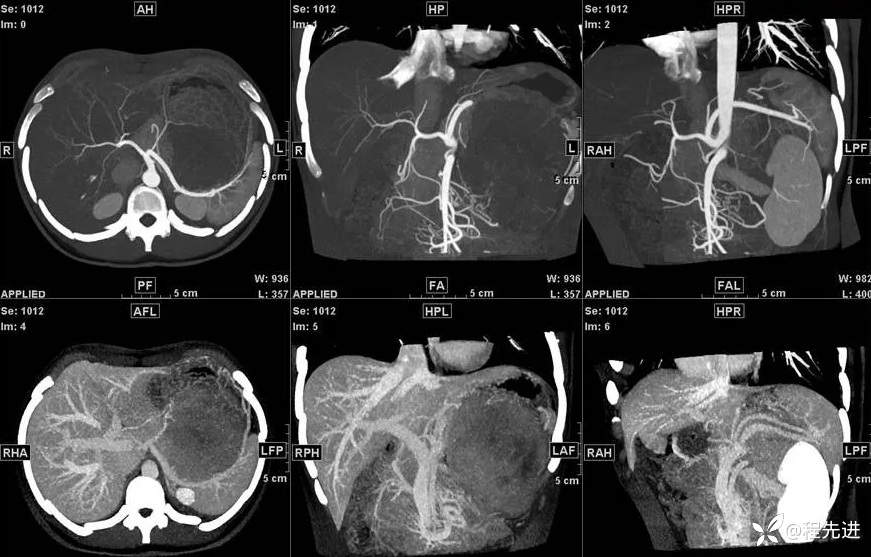

影像检查:

T1: